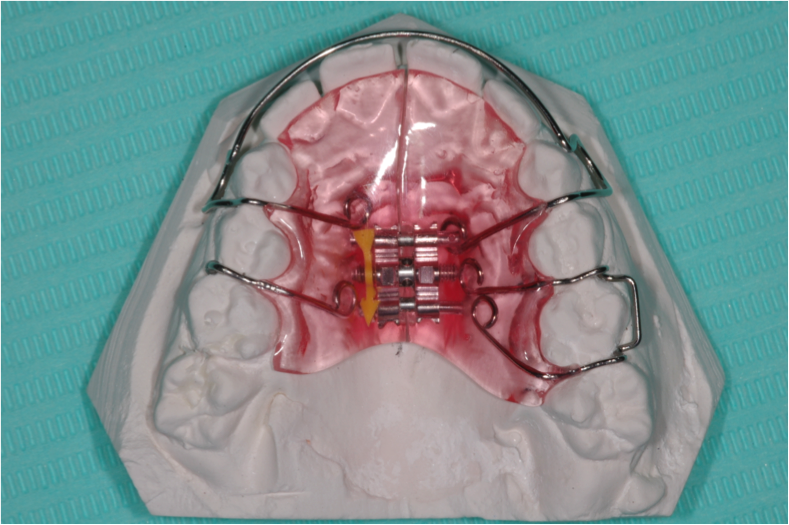

Les appareils amovibles, que le patient peut retirer. Les appareils ont divers ressorts et vérins, positionneurs.